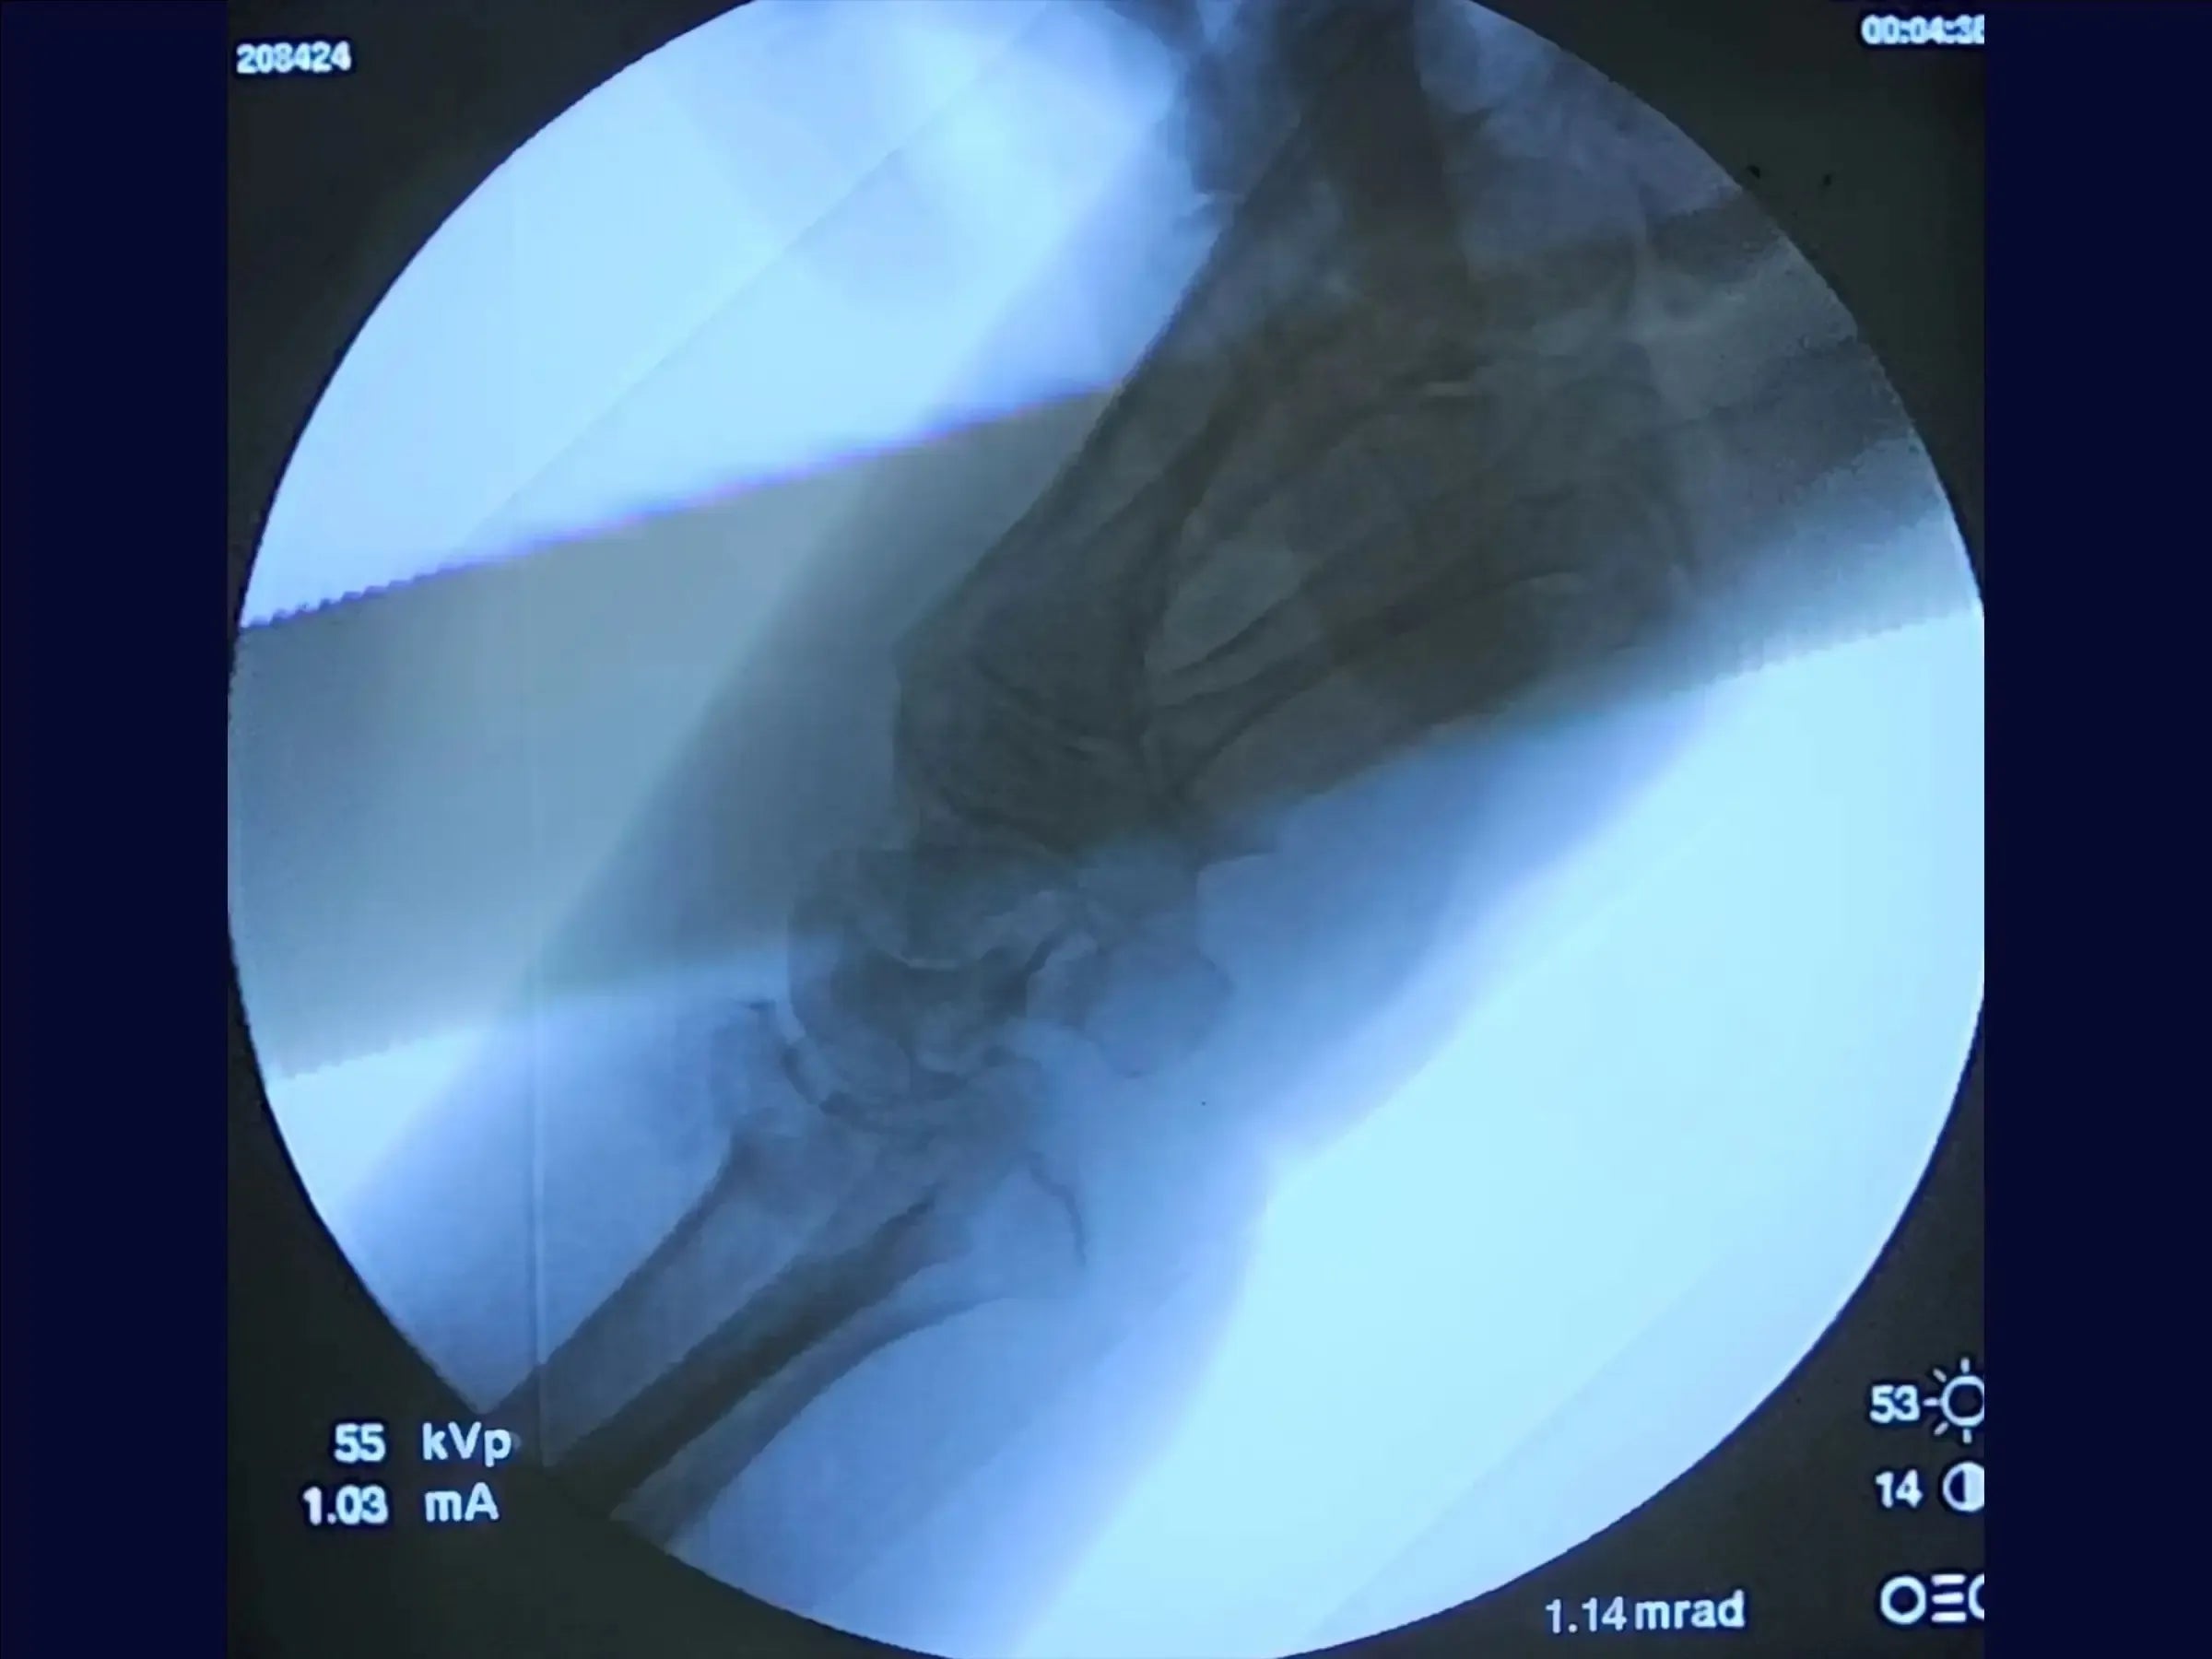

- Avaliação e Acesso Cirúrgico: O treinamento inicia com a avaliação radiográfica para planejamento da redução e implante. Aborda a demarcação do acesso sobre o tubérculo de Lister, identificação dos compartimentos musculares e rebatimento de tendões para expor a fratura.